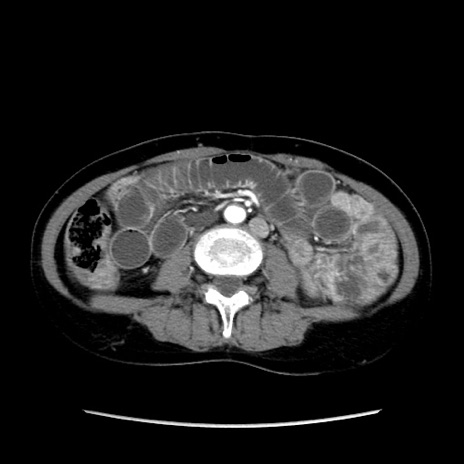

症例32(横断像)

【症例】40歳代 女性

【主訴】上腹部痛、嘔気・嘔吐

【現病歴】約9時間前頃から急に上腹部痛、嘔気、嘔吐が出現。改善しないため救急要請。

【既往歴】子宮頚癌(広汎子宮全摘術、放射線療法)、腸閉塞

【身体所見】腹部:平坦、軟、腸雑音亢進、上腹部を中心に腹部全体に圧痛あり。

【データ】WBC 8400、CRP 0.03